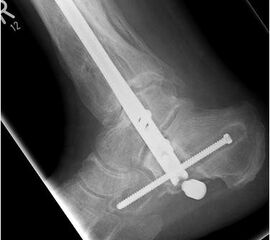

• Revision einer gescheiterten Fusion des OSG/ USG (Abbildung 3, Abbildung 4).

• Pseudarthrosen (Abbildung 5, Abbildung 6).